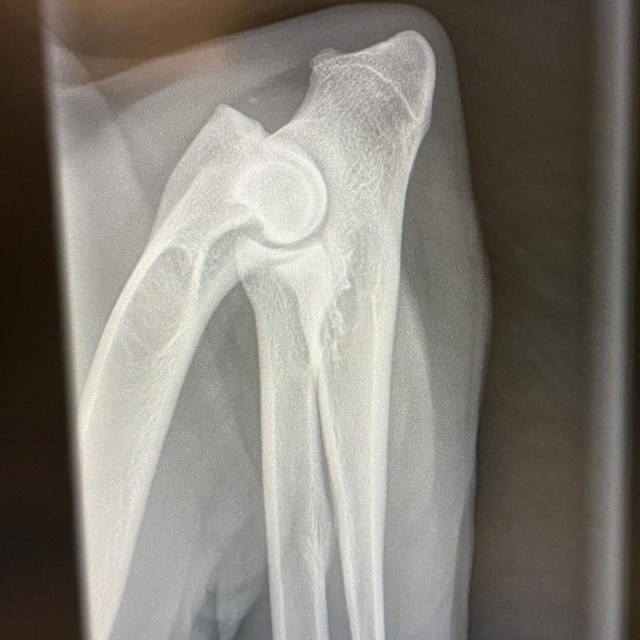

Vid röntgen mäter man förekomsten av pålagringar som uppstått på grund av defekten.

De graderas med graderna 0,1,2 och 3, där noll är inga pålagringar, 1 lindriga, 2 måttliga och 3 är kraftiga pålagringar.

Bild på en normal armbåge med grad 0